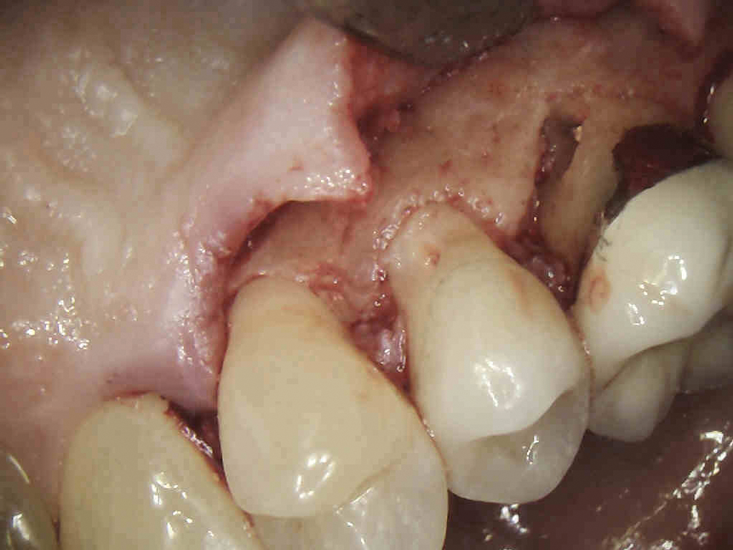

(2.) NSRCT, which had previously been completed on tooth No. 3, was also completed on tooth No. 4 prior to initiating surgical repair of the ECR lesions because it exhibited signs and symptoms of irreversible pulpitis.

Figure 2